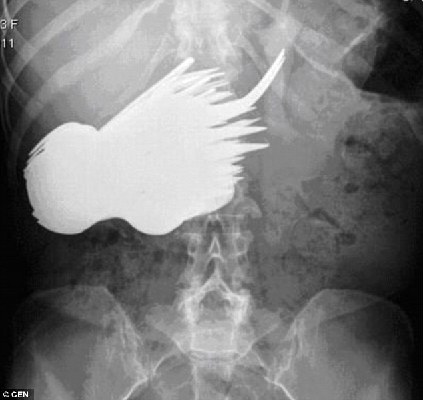

X光片顯示,瑪格麗特的胃里有很多餐具。

中國日報網環球在線消息:英國《每日郵報》28日披露,30年前,荷蘭女子瑪格麗特·達阿爾瑪因為胃痛難忍,到鹿特丹一家醫院檢查。診斷結果令人瞠目結舌:瑪格麗特的胃里竟然有78把銀制勺子和叉子。這段奇聞軼事直到最近才被德國一家醫學雜志曝光。

根據德國醫學雜志《精神病在線雜志》的披露,30年前,年僅22歲的瑪格麗特被查出胃里竟然有78把餐具。醫生立即為她實施了手術,將胃中的勺子和叉子一個接一個地取了出來。在場的醫生和護士十分不解,她為什么會吞餐具。